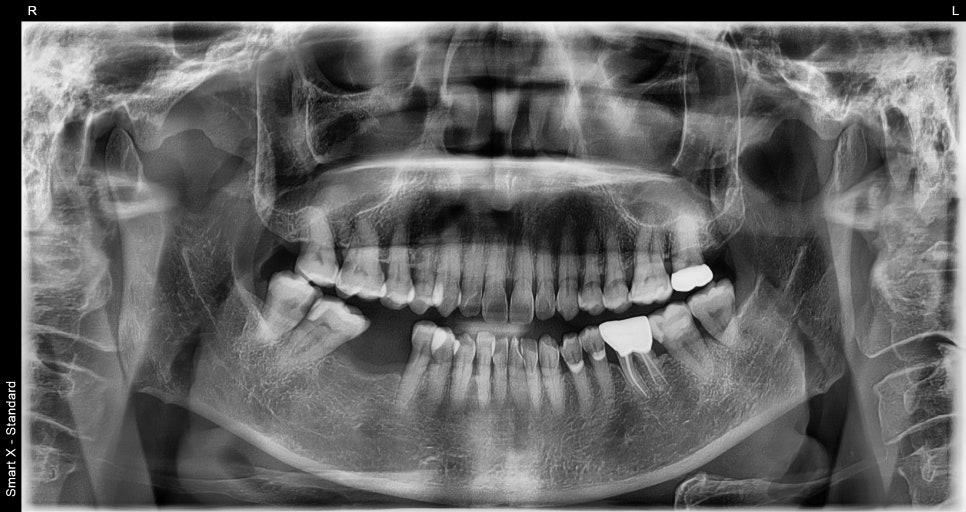

내원 당시 초진 엑스레이 사진

“예전에 뽑았던 어금니 자리, 요즘 들어 더 불편하고 음식도 잘 안 씹힌다”며 내원하셨습니다.

50대 외국인 여성분께서 내원해주셨는데,

파노라마 촬영 결과, 오른쪽 아래 첫 번째 어금니발치

상태로 방치되어 있었고, 양 옆 치아가 살짝 쓰러지기 시작한 모습이 보였습니다.